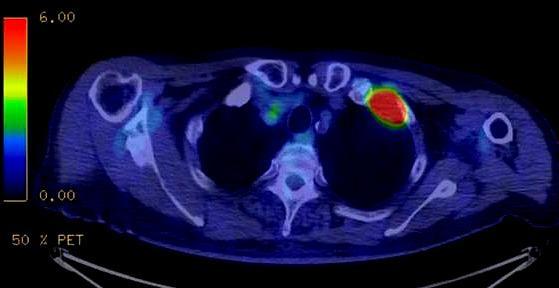

如果患者不仅肩痛明显,周身也存在着明显的疼痛,那么要进行骨扫描或者是pet ct检查,明确是否存在着骨转移。

图片